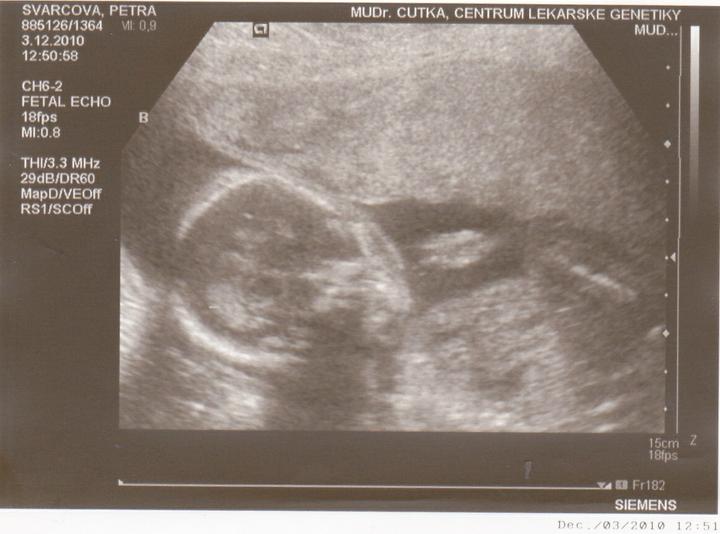

3.12-Jedu do Českých budějovic na ultrazvuk.Jsem zvědavá jak miminka povyrostly za ten měsíc co jsem tam byla naposled.Ale zároveń se bojím jestli jsou v pořádku.

Včera jsem Byla v Českých Budějovicíh.Jedno mimi váží 267g, a druhé váží 314g.A jsou to kluci.